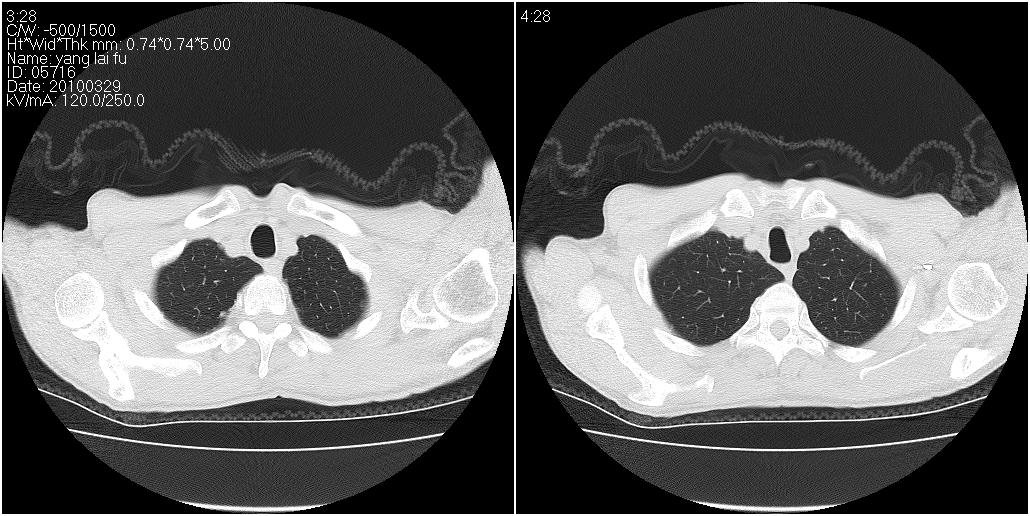

标题: CT25416:男性,70岁。胸片发现右下肺斑片状阴影 [打印本页]

标题: CT25416:男性,70岁。胸片发现右下肺斑片状阴影

以下是ct检查的情况:

右下肺阻塞性肺炎!建议纤支镜!

右肺中叶阻塞性不张及肺炎,高度怀疑支气管占位,建议纤支镜检查!

右中肺阻塞性炎症,建议纤支镜!双下支扩感染。